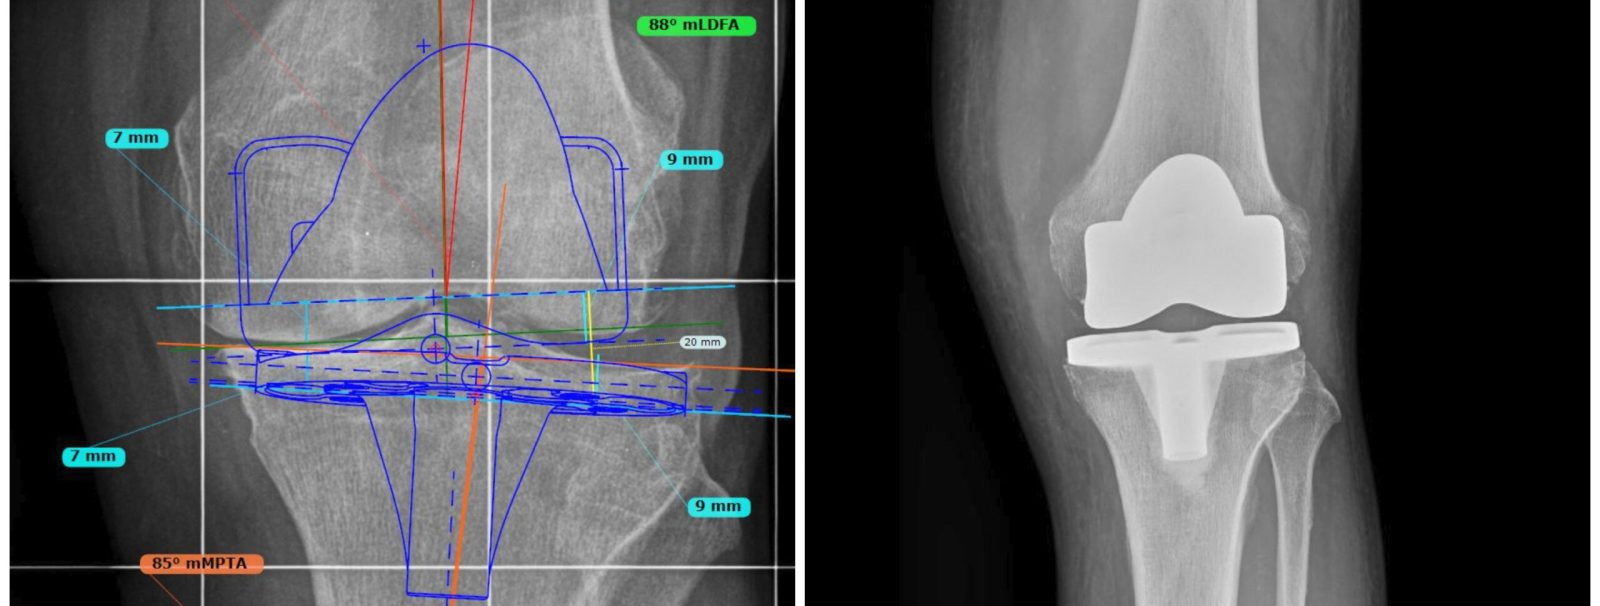

Analogamente alla progettazione di un ingegnere per poter avviare la costruzione di un edificio, l’atto chirurgico non può prescindere da un minuzioso planning preoperatorio, condotto sia su film radiografico che in modalità digitale mediante sofisticati software di pianificazione.